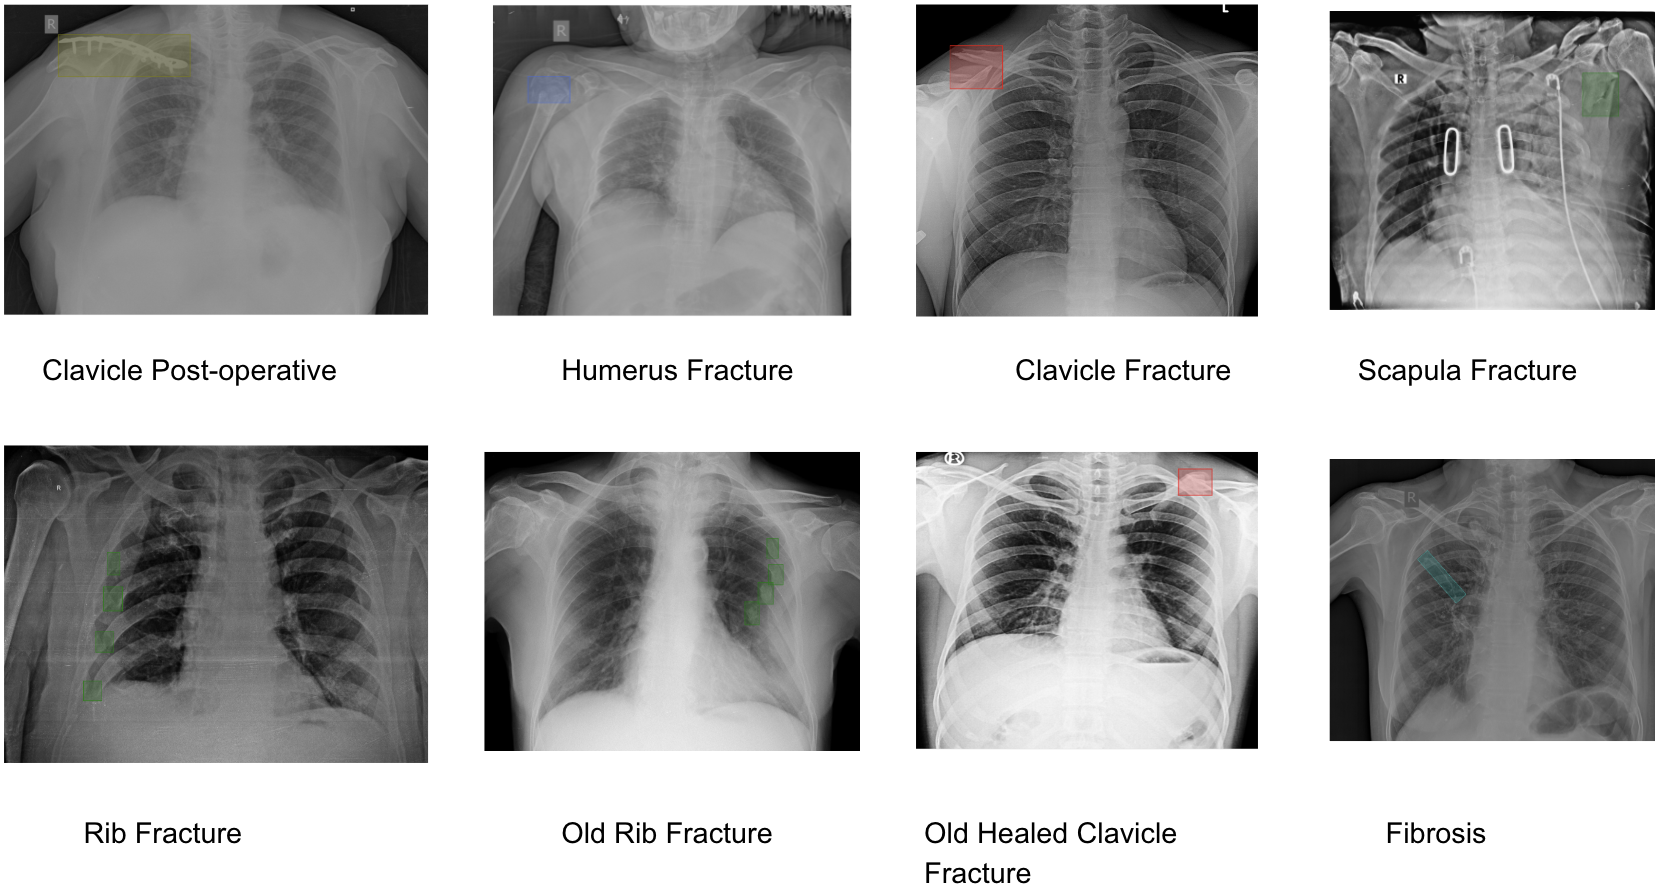

This paper presents an AI-based approach designed to address these challenges in the Indian healthcare system by enhancing CXR pathology detection capabilities. The system is capable of detecting 75 distinct pathologies, from common infections to complex thoracic conditions, using a combination of Vision Transformers for classification, Faster R-CNN for detection, and UNet for segmentation [5]. This multi-layered approach enables precise identification of abnormalities while automating the detection and reporting process. We begin by outlining the challenges in CXR reporting within India and describe how AI is uniquely positioned to tackle these issues [6]. The paper also elaborates on the methodology, covering the system architecture and workflow from input to pathology detection, aimed at providing accurate and actionable insights [7].

The AI system developed for this study is a computer-aided detection (CAD) tool designed for the identification and differentiation of various radiological abnormalities present in chest X-rays (CXRs). This system incorporates multiple deep-learning algorithms, each tailored to detect specific pathologies, covering a comprehensive range of thoracic conditions(Ronneberger et al., 2015). The models were trained on a large-scale dataset consisting of over 5 million CXR images, with expert radiologist annotations used for supervised learning(Firdiantika & Jusman, 2022). The AI system aims to detect abnormalities such as lung nodules, pleural effusion, pneumothorax, cardiomegaly, consolidation, fibrosis, hilar enlargement, rib fractures, etc.

Moving beyond classification, the detection capability of the model was evaluated using Precision, Recall, and Intersection over Union(IoU) metrics. Precision indicates how many of the abnormalities identified by the model were true positives, while recall measures the ability of the model to identify all existing abnormalities in the chest X-rays. IoU was utilized to evaluate the overlap between predicted regions of interest and the actual ground truth, offering a quantitative assessment of the model’s localization accuracy. Performance metrics for all 75 detected pathologies were documented, providing an in-depth view of how well the system performed for each specific condition. The metrics for precision, recall for each of these pathologies are presented in the table below, showcasing the AI’s proficiency in both identifying and accurately localizing abnormalities. These results highlight the system’s ability to support clinical workflows, enhancing both the accuracy and speed of radiology reporting.